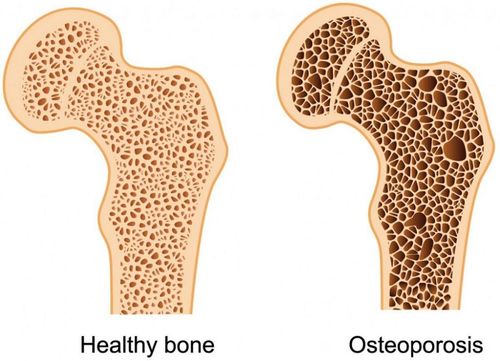

Gãy xương cành tươi là một loại gãy xương mà xương chịu lực uốn cong dẫn tới nứt gãy. Áp lực gây ra sự gãy xương không tách nó thành từng phần. Gãy xương cành tươi thường được gọi là gãy xương một phần hoặc không hoàn toàn, chỉ gãy một phần ở thân xương trong đó vỏ xương một bên bị gián đoạn, bên còn lại vỏ xương vẫn còn nguyên.

Gãy xương cành tươi thường gặp ở trẻ nhỏ, đặc biệt là ở độ tuổi dưới 10 tuổi. Bởi vì xương trẻ em phần lớn là sụn chưa cốt hóa, sụn này có chức năng kéo dài xương trong quá trình phát triển của trẻ. Nên xương trẻ em thường mềm hơn và linh hoạt hơn xương người lớn. Khi chịu lực tác động nó không dễ gãy thành mảnh rời mà chỉ gãy một phần. Tuy nhiên, gãy xương cành tươi có thể gặp ở tất cả mọi lứa tuổi.